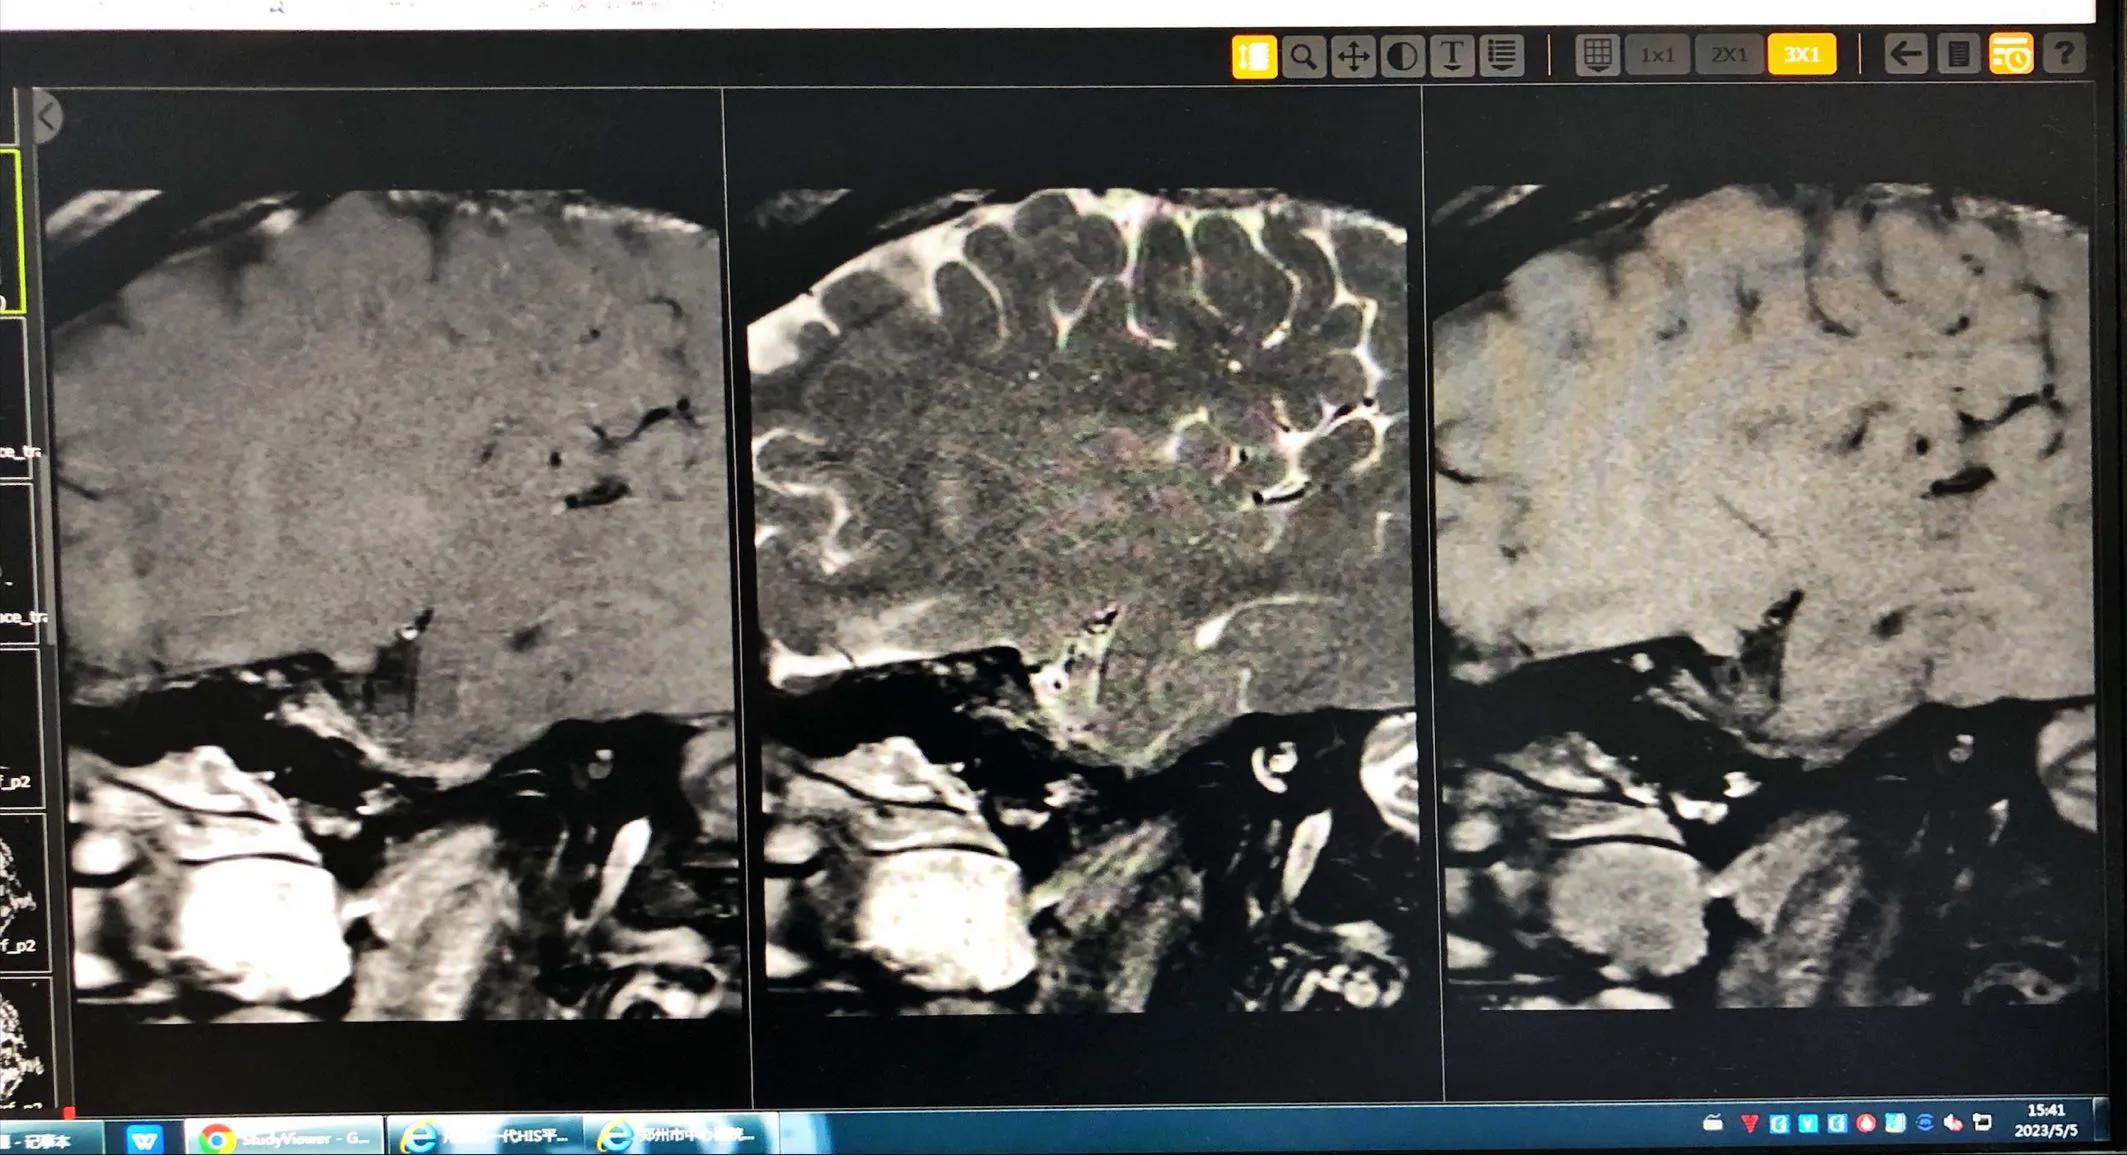

病例2.男,28岁,以“言语不清、右侧肢体无力4天”为主诉入院。2、既往史:否认“高血压、糖尿病、冠心病”病史抽烟2包/天·10年,喝酒;4天前喝酒半斤后患者出现言语不清、右侧肢体麻木无力,不伴有头痛呕吐,无听力下降、复视、饮水呛咳、吞咽困难及意识障碍,无大小便*禁失**,症状持续不缓解,就诊于河南省第三人民医院,查头MRI提示(河南省直第三人民医院 2020.08.20)示:1.左侧基底节区、额顶叶脑梗塞(急性期),2.头颅动脉血管硬化性改变,椎-基底动脉迂曲,3.双侧大脑中动脉及左侧大脑前、后动脉局限狭窄,4.左侧大脑中动脉分支稀疏,诊断为“急性脑梗死、脑动脉狭窄、烟雾病?”,治疗(具体不详)后症状有减轻,为求进一步明确病因诊治来我院,以“脑梗塞”收入我科。查体:BP140/105mmHg,神清、不完全运动行失语、中枢性面舌肢瘫、右上下肢肌力 Ⅳ级,粗测无明显感觉,右侧巴氏征(±)NIHSS评分4分。I、 左侧大脑中动脉斑块分析:1.左侧大脑中动脉斑块分析M1段局部管腔 中度 狭窄,并斑块形成,考虑不稳定斑块;

图片来源于病历

2.PWI:左侧侧脑室旁达峰时间(TTP)、平均通过时间(MTT)稍延长 ;造影情况如下: